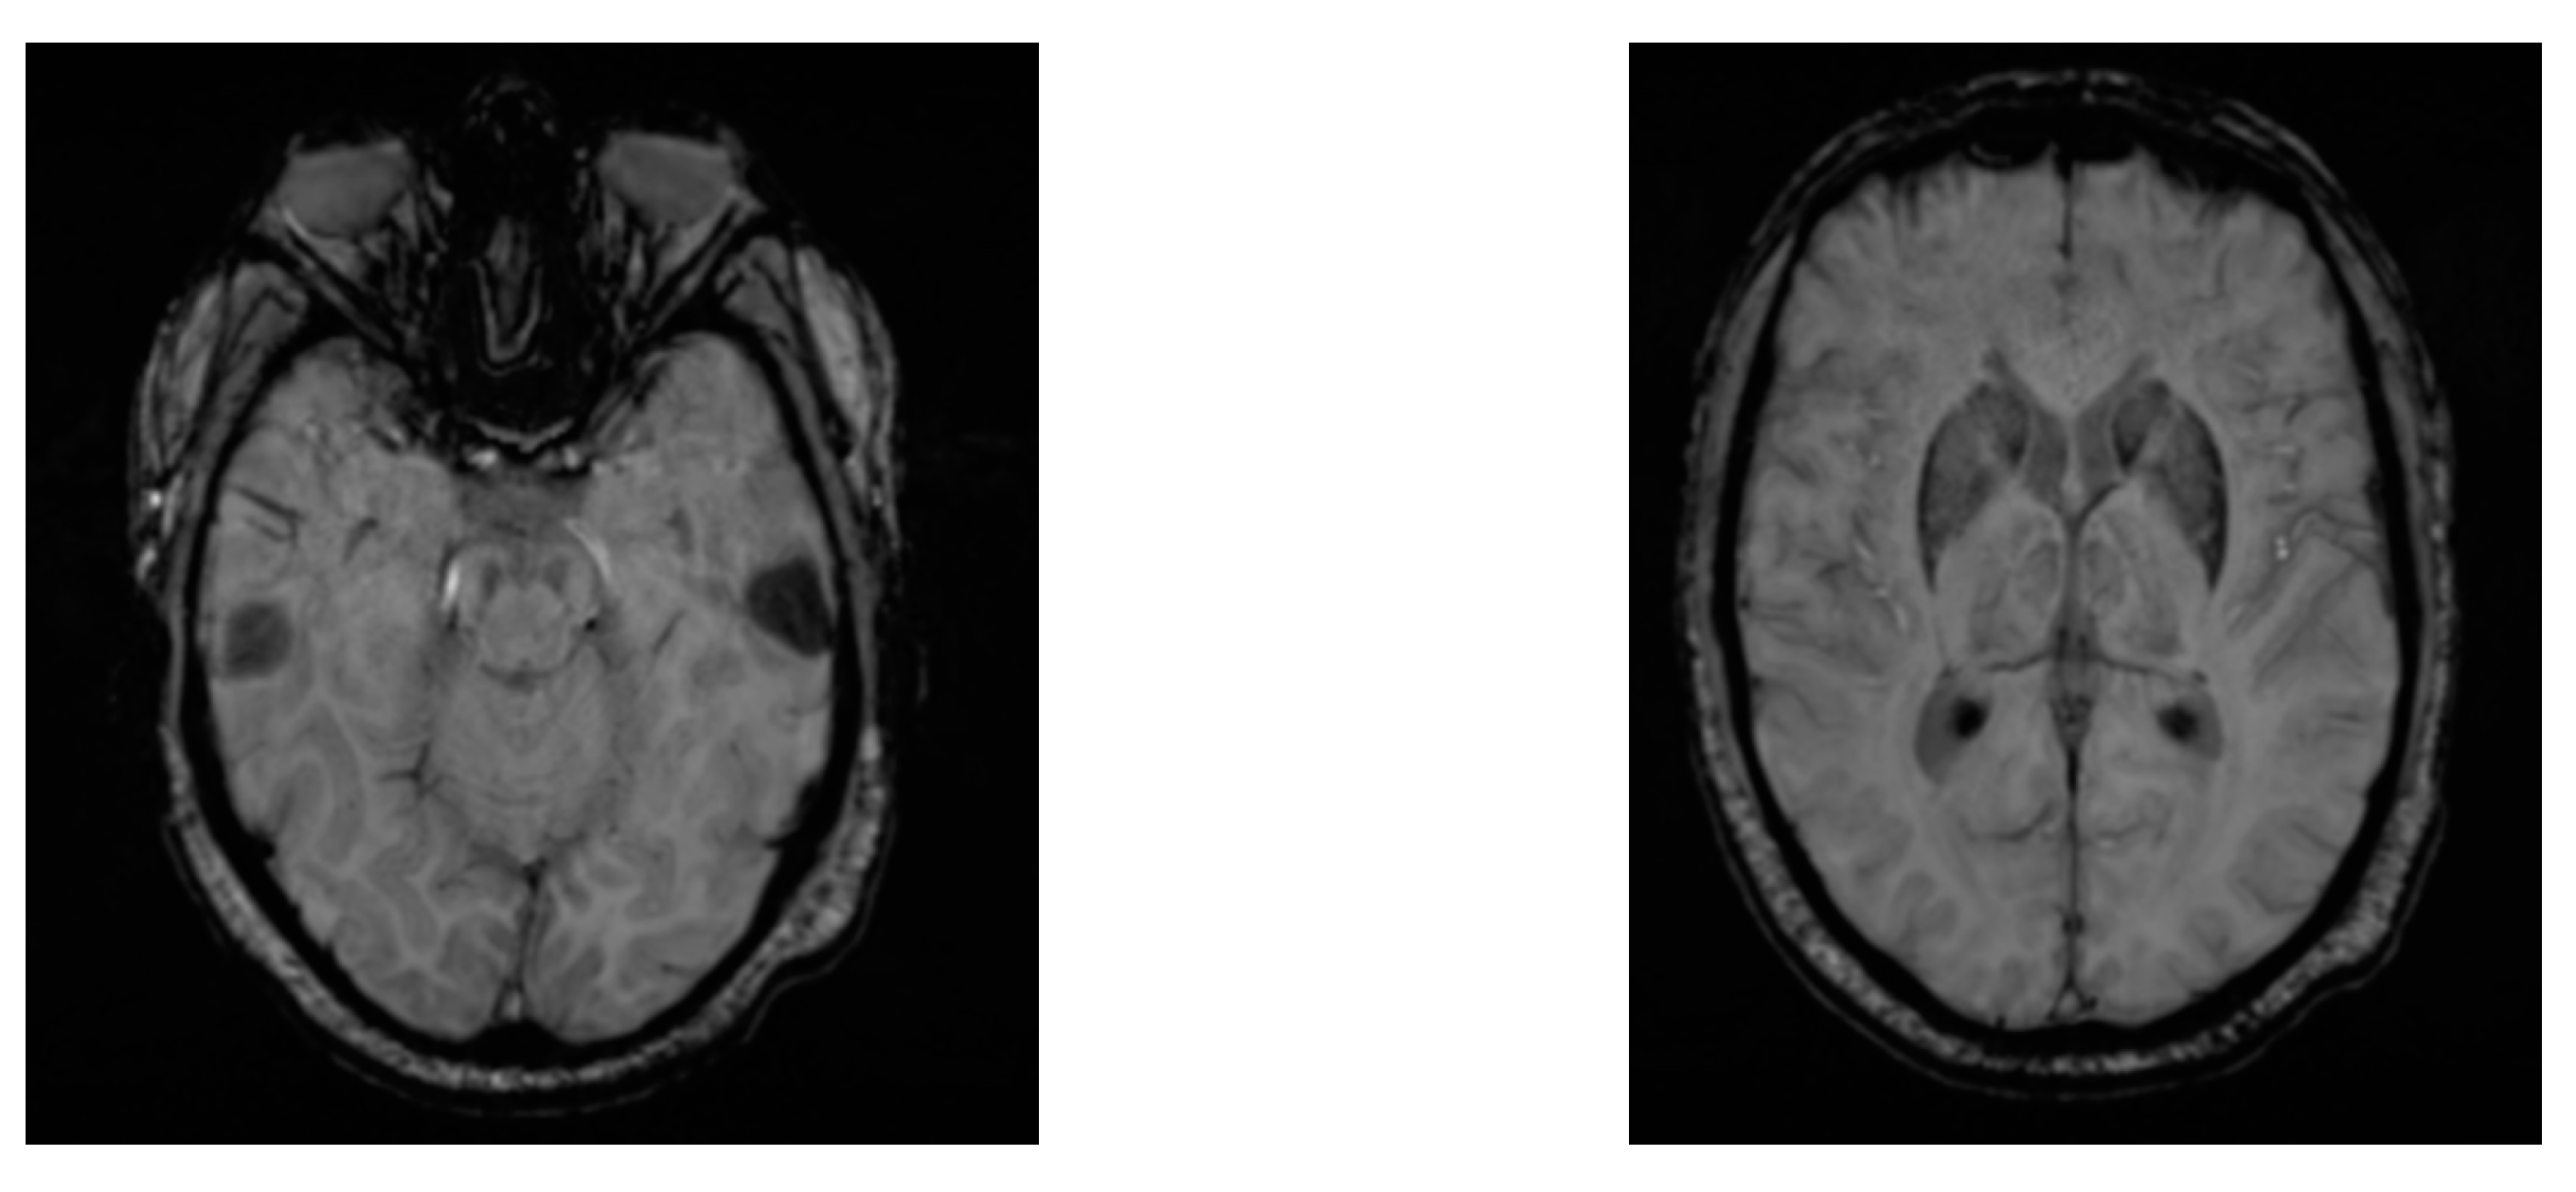

3.2. MRI for PD Identification

| Zhang et al. [33] | Prodromal PD Detection | 102 AXI/SAG MRI | WGAN/ResNeXt | Accuracy: 76.5% | Limited performance, complexity of approach |

| Ramirez et al. [34] | De Novo PD Detection | DTI MRI (129 de novo PD and 57 Controls) | Convolutional Autoencoder | AUC: 83% | Limited performance, small dataset |

| Prasuhn et al. [35] | PD Detection | DTI MRI (162 PD and 70 Controls) | bSVM, MKL | AUC: 58%, 60% | Low performance |